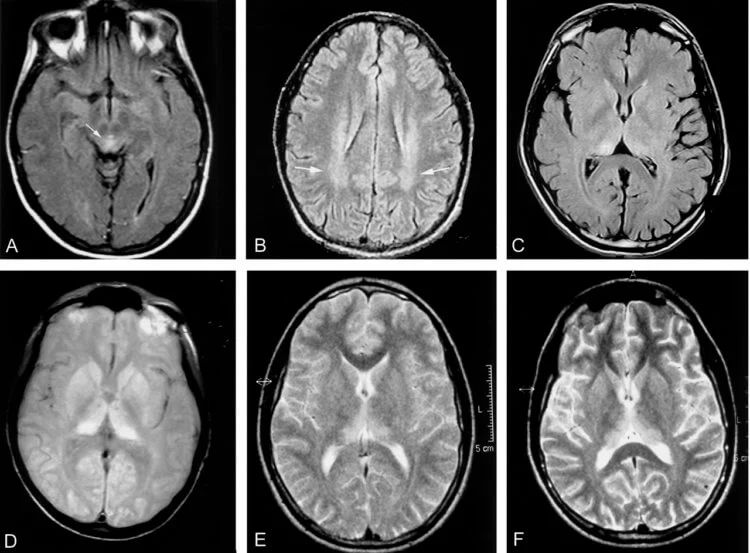

Сканирование мозга пациента с болезнью Крейтцфельдта-Якоба.

Дальнейшая работа с использованием магнитно-резонансной томографии и рентгеновской кристаллографии должна помочь исследователям понять ключевые структурные элементы, которые позволяют прионам вызывать заболевание. Вполне вероятно, что другие клеточные компоненты помогают им в этом процессе, поэтому работа над пониманием клеточной биологии обеих форм белка жизненно необходима.